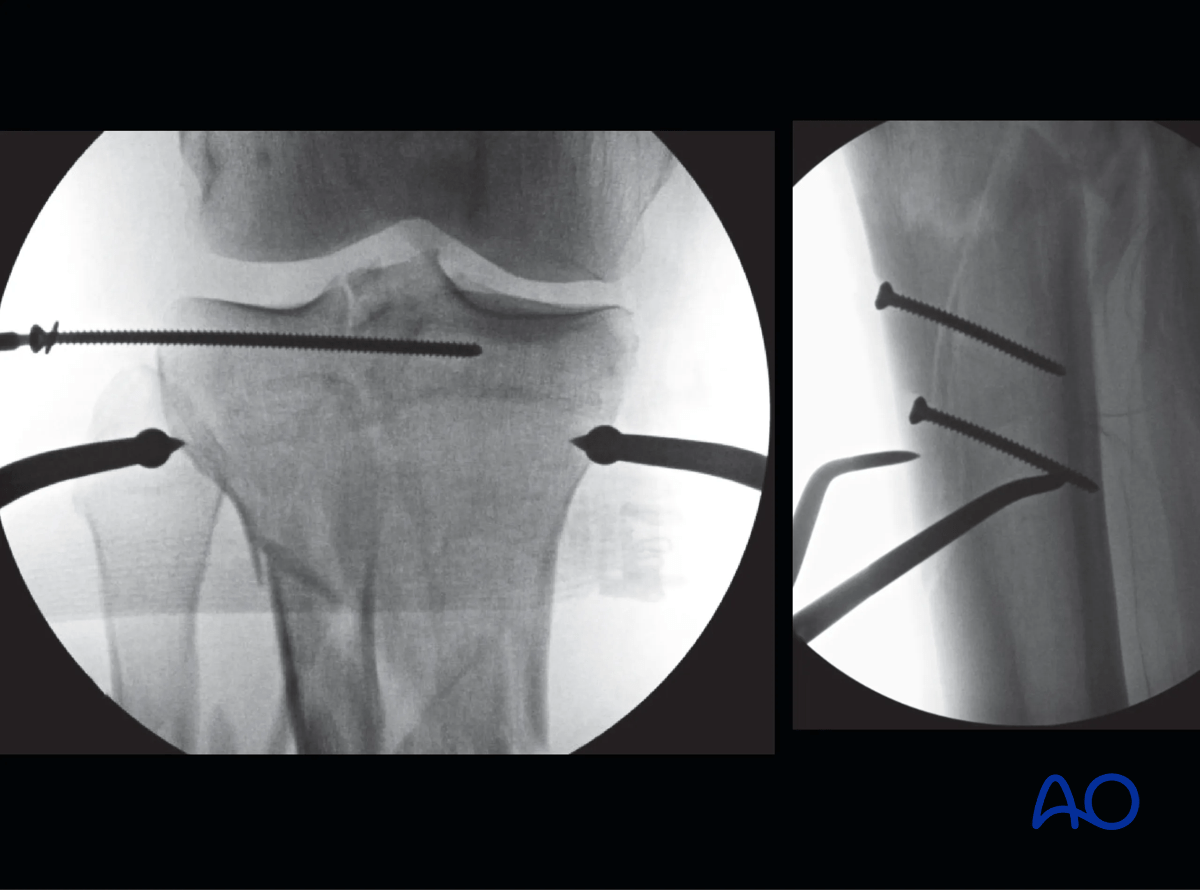

A smooth wire is then placed in the frontal plane from lateral to medial, orthogonal to the long axis of the tibia approximately 1.5–2 cm distal to the articular surface and distal to the lag screws. The articular ring is then positioned at the level of the wire by lengthening or shortening the threaded rods as needed. Care should be taken to check axial alignment of the articular block in both AP and lateral views.

Note: Placing wires closer than 1.5 cm to the subchondral bone may result in an intraarticular wire and become a source of infection in the joint.

Proximal tibia fracture – ring fixation: fracture fixation

The wire is then secured to the articular ring and tensioned. Care should be taken at this point to assess and correct varus-valgus alignment of the articular block with washers on the reference wire.

Proximal tibia fracture – ring fixation: tensioning a wire secured to the articular ring

It is important to evaluate the sagittal alignment in the lateral image at this point to correct any flexion/extension deformities. Additional fixation of the articular block is via a pair of olive wires from either side of the proximal ring as widely divergent as the soft tissue will allow. This pair of olive wires will control translational movement of the proximal segment.

Proximal tibia fracture – ring fixation: fixation of the articular block